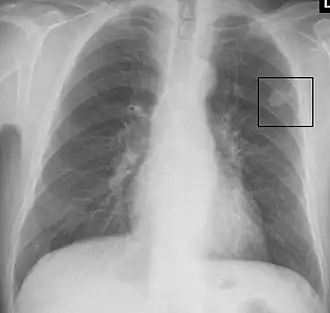

- Рак верхушки лёгкого с синдромом Панкоста

- Рак лёгкого